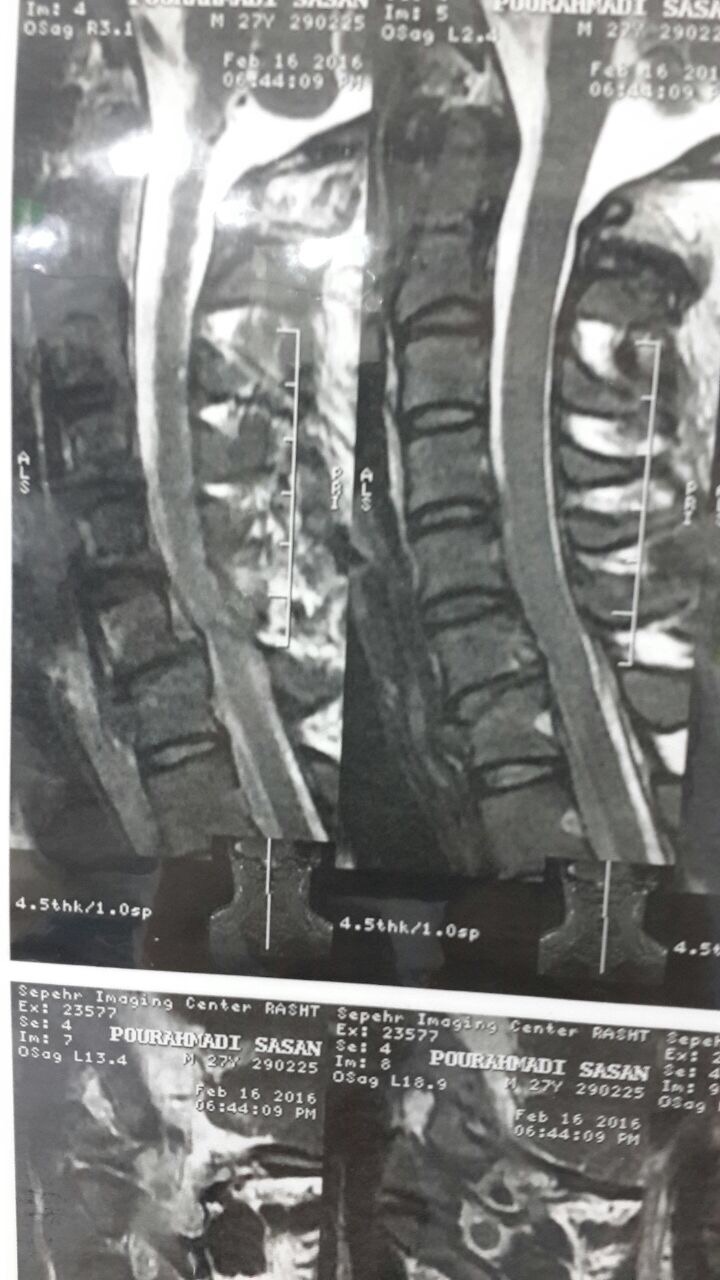

بیمار جهت بررسی بیشتر به بیمارستان شهید بهشتی بندرانزلی اعزام شد که بلافاصله برای بیمار CT فقرات سرویکال و نیز MRI در خواست شد.

شکستگی مهره C7گردنی همراه با درگیری کانال نخاعی وجود داشت که در صورت عدم جراحی سریع می توانست باعث فلج هر4 اندام بیمار شود.